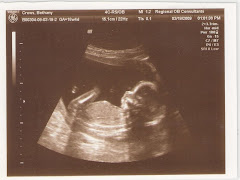

19 week sonogram

This past Thursday we went for our 19 week sonogram. They checked out the baby's heart, kidneys, and back bone. They also took several measurments to make sure that the baby was growing properly. After about 15 min. of playing with my belly to get the baby to move around it finally decided to wake up and cooperate. Once it copperated they were able to determine that it is a very healthy baby boy with vey long toes. Everything is looking good so far. I have had some morning sickness but it has pretty much settled down now. The Baby still does not like me waking up early for work so I normally get sick once every morning, but then I'm good to go. We went Friday night with my Mom and my Grandma to work on our registry and after a couple hours of Ronnie, Mom, Christen, Grandma, Papa, and me wondering around we got the registry at Babies R Us finished. I hope everyone enjoys the pictures and if you have any questions or comments please leave them I will try and keep the blog updated regularly. Love you all!